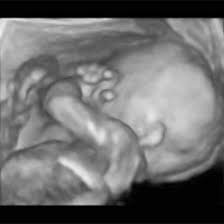

Baby development at 20 weeks. He's just being measured differently. Here is more about the weight of your baby, placenta, and other parts at different stages in pregnancy. Calculate baby's weight at that week of the pregnancy. Your little one weighs only about 3 pounds at week 30 of pregnancy.

No, your baby didn't really grow 4 inches since last week. Much of that weight comes from growing organs, bones, muscle and accumulating baby fat. A baby can more than double their weight in only about 10 weeks. You've got a heavyweight in your belly at 20 weeks pregnant (well, in baby terms, anyway). This is because a baby's legs are curled up against his torso during the first half of pregnancy and very hard to measure.

Everyone keeps saying how small i am for 21 weeks, this is my 3rd pregnant but lost 2nd. They weigh about 10.2 ounces and measure about 6.5 inches from crown to rump. Feedings take longer and each bite becomes bigger and they gain weight faster. No, your baby didn't really grow 4 inches since last week. Wouldn't you like to know what your baby weighs when you are in your 20th week of pregnancyc while the average weight gain at 20 weeks for pregnant women is 10 pounds or so, most babies weigh around 9 ounces at this timem.